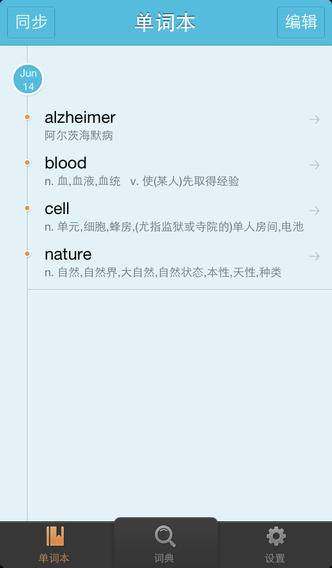

医药大词典 专注于医学,由中国最大的医药专业网站丁香园开发。收录百万医学词汇,提供医学专业释义、音标、论文例句。功能介绍1. 拷贝查词:在其他App拷贝单词即可发起查询,释义自动浮现,不会打断您的阅读。2. 单词本:收藏至单词本,背单词更轻松。单词本可同步至云端,数据更安全。3. 离线查词:专业版可安装多个离线词库,查询无需联网,更节省流量。4. 论文例句:海量医学中英例句,为您的科研写作提供优质素材。关于丁香园丁香园生物医药科技网(DXY.CN)成立于2000年7月23日,自创办以来一直致力于为广大医药生命科学专业人士提供专业交流平台。凭借着专业精神和深厚积累,专业交流不断深入和发展,丁香园已从最初每天只有数人查看的留言板逐步发展壮大成为国内规模最大、最受专业人士喜爱的医药行业网络传媒平台。联系我们Email: app@dxy.com微博:@丁香园